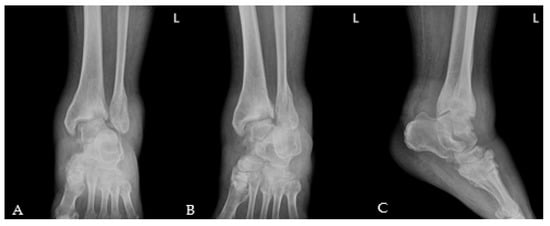

2. Case Presentation

2.1. Preoperative Evaluation